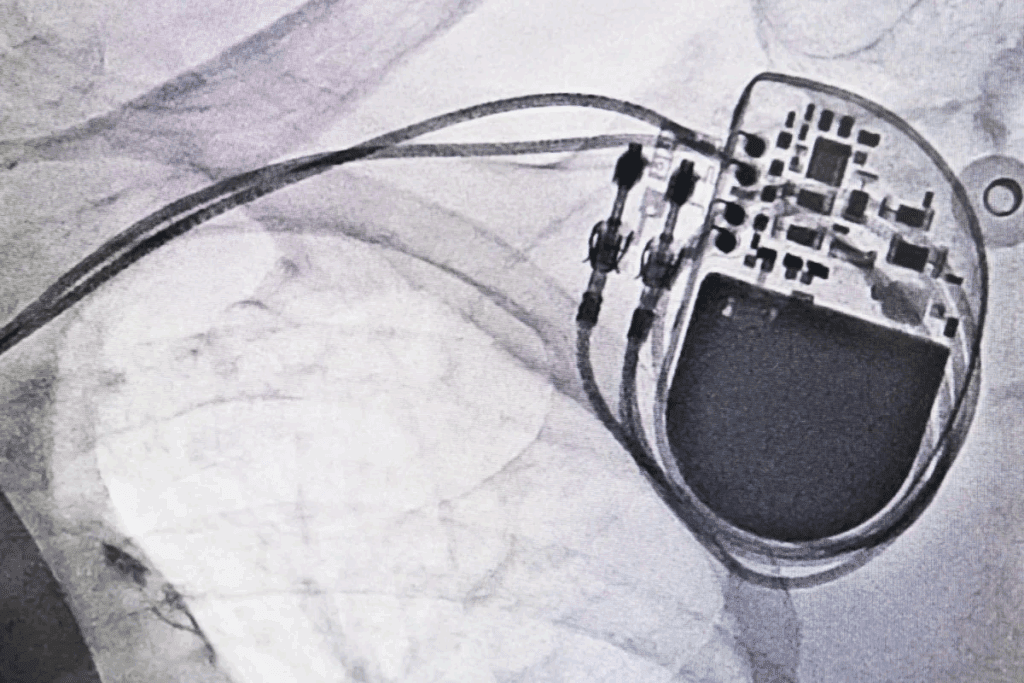

The Basics of Cardiac Pacemakers

Understanding pacemakers is key for managing heart conditions like AFib. A pacemaker is a small, battery-powered device. It prevents the heart from beating too slowly. The Medical organization says pacemakers keep the heart’s rhythm regular.

How Pacemakers Function

Pacemakers send electrical impulses to the heart. This makes it beat at a regular rate. They are programmed to fit the patient’s needs, adjusting the heart rate based on activity.

Types of Pacemakers Available Today

There are many types of pacemakers, each for different needs. The main types are:

- Single-chamber pacemakers

- Dual-chamber pacemakers

- Biventricular pacemakers

The Implantation Procedure and Recovery

The implantation procedure involves a small incision in the chest. The pacemaker is placed under the skin. Leads are guided through a vein into the heart. Recovery usually includes a short hospital stay for monitoring.